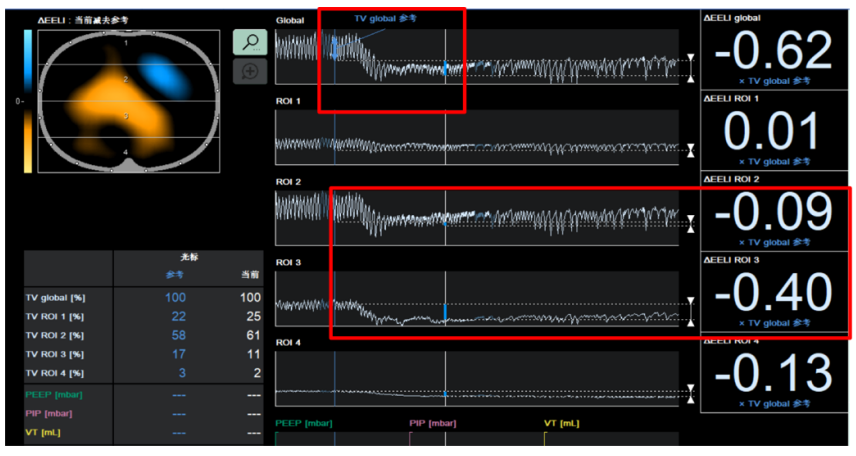

通过电阻抗断层成像(EIT)监测也可以发现肺容积在短时间内明显下降,尤其在肺的重力依赖区(图2)。这可能与低通气有关。低通气可导致肺不张、肺顺应性降低、肺部感染加重、右心功能衰竭等。

图片

图2  ECMO前后EIT指标变化